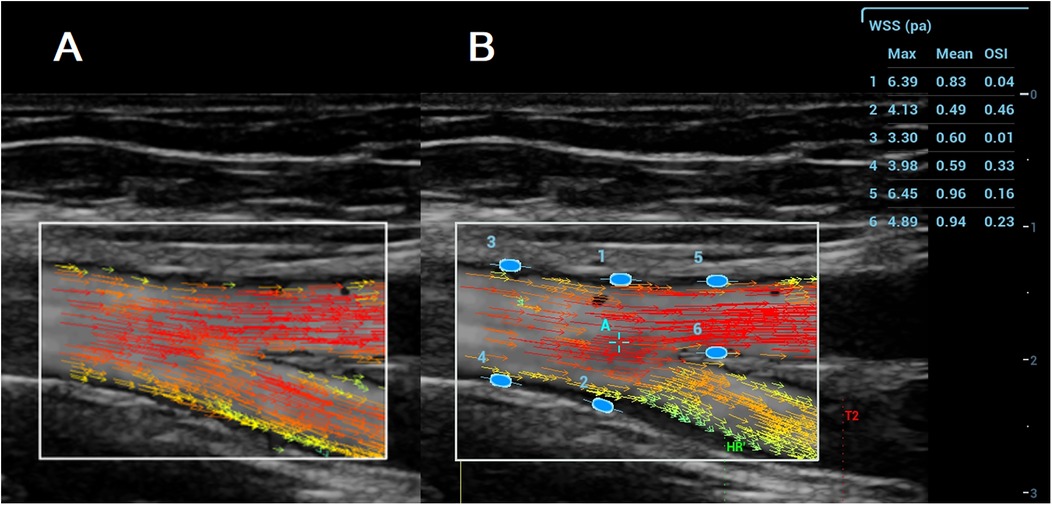

In the VFI image, a series of arrows in different colours represented blood flow direction and velocity (Figure 2A). VFI cine loops were saved on the ultrasound system and transferred to a USB drive.

Vector Flow Ultrasound image showing blood flow in an artery, with colored arrows indicating velocity and direction. Panel A presents a side view with red, orange, and yellow arrows. Panel B displays a labeled view, featuring additional blue ellipses numbered one to six for Wall Shear Stress (WSS) measurement. A table on the right lists the WSS and Oscillatory Shear Index (OSI) values for each ellipse.

Figure 2. A (left): VFI image of the femoral artery bifurcation recorded with the resona 7. Arrows in different colours represent blood flow direction and velocity; B (Right): Maximum WSS, mean WSS, and OSI measured with the Resona R9T. Numbers 1–6 indicate locations for maximum WSS, mean WSS, and OSI measurement, along with their corresponding results for maximum WSS, mean WSS, and OSI.

VFI cine loop files recorded on the Resona 7 were transferred via USB and analyzed on the Resona R9T system. After selecting a target frame, the operator tapped [WSS], which generated a green ellipse on the screen. The ellipse was positioned and oriented at the vessel wall (A1–A10), and pressing [Set] fixed the measurement site. Maximum WSS, mean WSS, and OSI were displayed in a results window on the right side of the screen (Figure 2B). Measurements were obtained at both the near and far walls of each site. All measurements were performed by MG and YL.